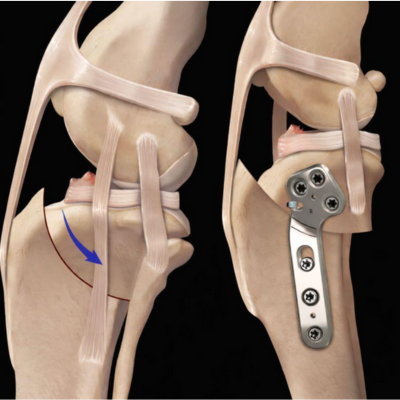

Deux grandes approches :

Techniques extra-articulaires (prothèses) : remplacent le ligament rompu par un système synthétique. Adaptées aux chiens de petite taille, elles offrent souvent un retour fonctionnel satisfaisant, mais présentent des limites mécaniques chez les chiens lourds et athlétiques.

Ostéotomie tibiale (TPLO) : modifie la géométrie du tibia pour que le ligament croisé ne soit plus nécessaire à la stabilité. Le fragment tibial supérieur est pivoté et fixé par plaque et vis. Cette technique offre une récupération plus rapide, des résultats fiables (95 % de succès) et protège le genou opposé. (Voir la fiche santé info TPLO)